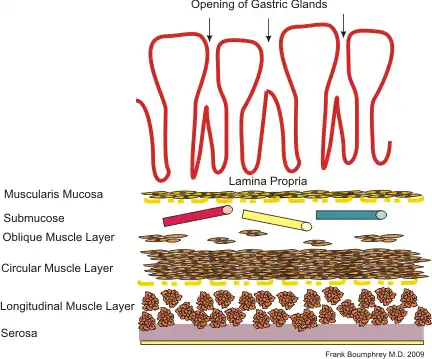

The GI tract is essentially a hollow tube connecting the mouth to the anus. The GI tract has a similar layout through out its length:

- An inner mucosal layer with an epithelial lining

- A submucosal layer

- A thin layer of muscle , the Muscularis Mucosa is at the junction of the mucosal and sub mucosal layers, outside this are the nerves of the mucosal plexus

- A muscular layer with an inner circular muscle layer and an outer longitudinal layer

- Between the muscles are the nerves of the myenteric plexus

- A serosal layer which is continuous with the mesentry

This is illustrated graphically here:

General Anatomy

Mucosa

The mucosal layer consists of a epithelial layer, and its underlying supportive tissue, the Lamina Propria. It is separated from the submucosal layer by the Muscularis Mucosa. The epithelial layer varies from section to section of the gut. In the oesophagus it is a non-cornified stratified squamous epithelium; in the stomach it is mainly mucosal cells; the small intestine and large intestine are characterized by absorptive cells, with many mucous producing goblet cells. In the absorptive sections of the intestine, the surface are for absorption is greatly increased by finger-like projections into the lumen called villi, and the absorptive cells themselves also have small projections of microvilli, giving them the appearence of a brush border when viewed with a light microscope.

The lamina propria contains lymph and blood vessels which drain into larger vessels in the submucosal layer. Also in the lamina propria, particularly in the absorptive layers are numerous immune cells, wandering macrophages and lymphocytes, as well as aggregations of lymphoid tissue called called Peyers patches. By some estimates 80% of the body's lymphoid tissue is in the intestine.

Submucosa

The submucosa consists of connective tissue with larger blood and lymph vessels. It is separated from the mucosa by the muscularis mucosa. Also in the submucosal layer is the submucosal plexus, part of the enteric nervous system. The muscularis mucosa probably acts to propel the contents of the mucosal glandular lumens and crypts (see below) into the lumen and also to enhance contact of the cells with the contents of the lumen.

Muscular Layers

Consists of an inner circular muscle, and an outer longitudinal muscle. Between the two layers is the mesenteric plexus, also part of the enteric nervous system. In the stomach there is also an oblique layer of muscle fibers interior to these two. The musclar layers work in harmony to produce peristaltic contractions and segmental contractions.

Serosa

The serosa is a continuation of the peritoneal membrane. It is useful to think of the gut as being envaginated into the peritoneal membrane until it completely surrounds it. The double layer of membrane as it attaches to the gut is called the mesentery, and it contains the main vessels and the non-intrinsic nerve supply to the gut.

The basic layout pattern holds true in the stomach, although the stomach has a third inner layer of oblique muscle fibers. The mucosal layer has numerous pits opening into the lumen, the mouths of the gastric glands. Some of these glands penetrate down into the submucosal layer.